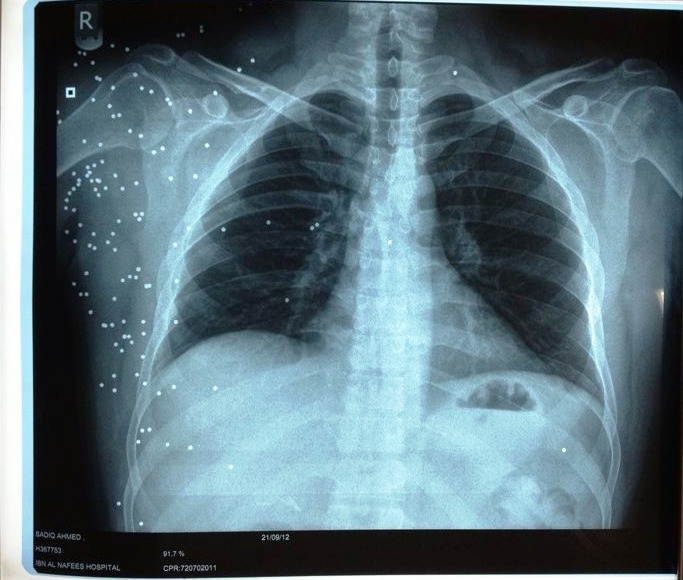

مرآة البحرين: أكدت «شبكة 14 فبراير الإعلامية» أن العضو البلدي الوفاقي السابق صادق ربيع، الذي أصيب برصاص «الشوزن» خلال قمع مسيرة سلمية في سترة منذ أسبوعين، فقد نسبة من سمعة من جراء الإصابة وما زالت شظايا "الشوزن" في جسده.

ونقلت الشبكة عن ربيع الموجود في مستشفى السلمانية قوله إنه أصبح يتبول دماً بعدما أدخل له أنبوب أثناء الاغماء تسبب له لجروح في المسالك البولية، مضيفا أنه بسبب تأخير العلاج فقد نسبة من سمعه وما زالت هناك شظيتان في رئته واربعةً أخرى في الكبد، والعشرات من الشظايا في جسده تهدد حياته.